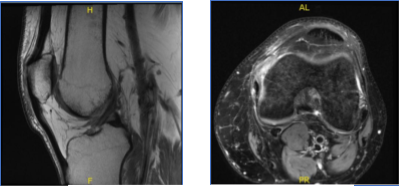

MRI-3T Left Knee Non-contrast

Results for MRI were presented and shown sprain of the medial collateral ligament, without evidence of high-grade tears. Longitudinal vertical tear involving the outer third of the body and posterior horn medial meniscus.

MRI-3T Left Knee Non-contrast

After a few months the patient visited for a follow up and presented the results of his MRI and shown signal alteration the posterior horn medial meniscus may represent a site of primary repair of the medial meniscus tear. Correlate with surgical history. No new tear is visualized. Trace joint effusion. Small quadriceps enthesophyte.

MRI-3T Left Knee Non-contrast